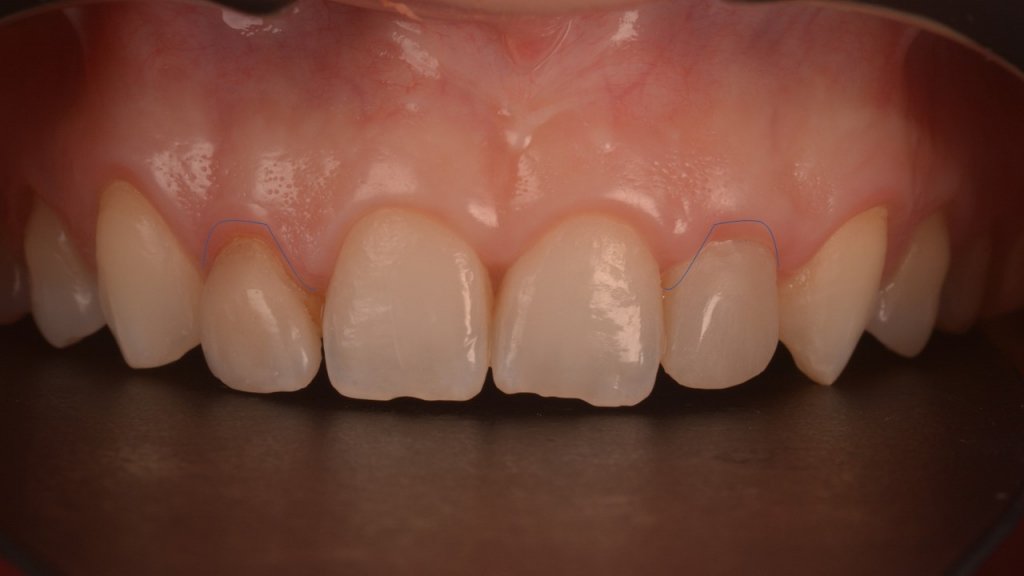

Me cuenta que ya en pasado, a los 18 años, se sometió a una ortodoncia y intentar enmascarar la microdoncia de los laterales con unas «carillas cerámicas». Esto era el resultado de dicho tratamiento:

Antes de la retirada había alargado los dientes a través de una cirugía «semiabierta», para regularizar el festoneado gingival:

Todos sabemos que el Mock-up es fundamental para revisar cositas y mejorar el resultado. Pero en este caso decidí utilizarlo también como soporte para estos dos cenits «recidivantes»